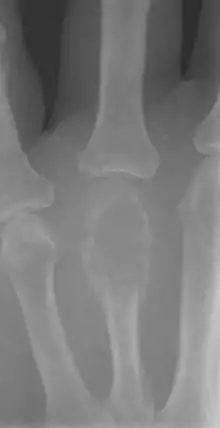

X-ray of a giant-cell bone tumor in the head of the fourth metacarpal of the left hand

On X-ray, giant-cell tumors (GCTs) are lytic/lucent lesions that have an epiphyseal location and grow to the articular surface of the involved bone.[8] Radiologically the tumors may show characteristic 'soap bubble' appearance.[9] They are distinguishable from other bony tumors in that GCTs usually have a nonsclerotic and sharply defined border. About 5% of giant-cell tumors metastasize, usually to a lung, which may be benign metastasis,[10] when the diagnosis of giant-cell tumor is suspected, a chest X-ray or computed tomography may be needed. MRI can be used to assess intramedullary and soft tissue extension.